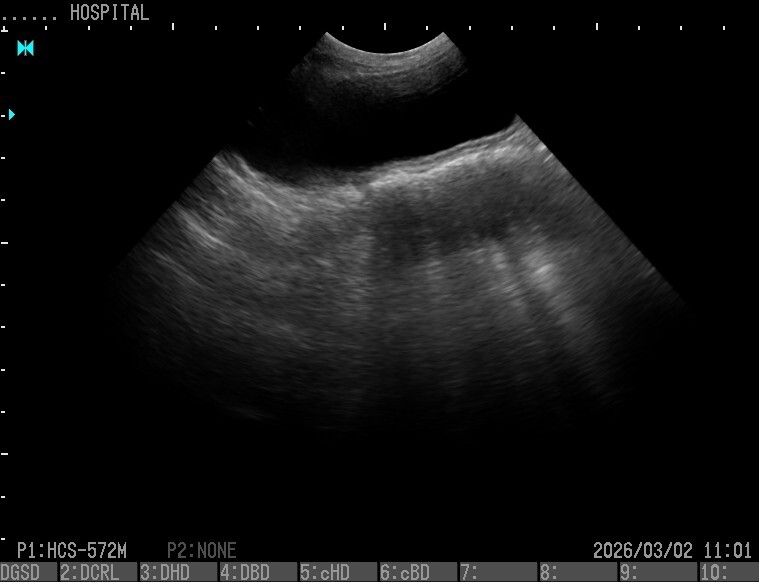

2.膀胱(中型犬)

プローブ:HCS-572M

H-res:Detail2